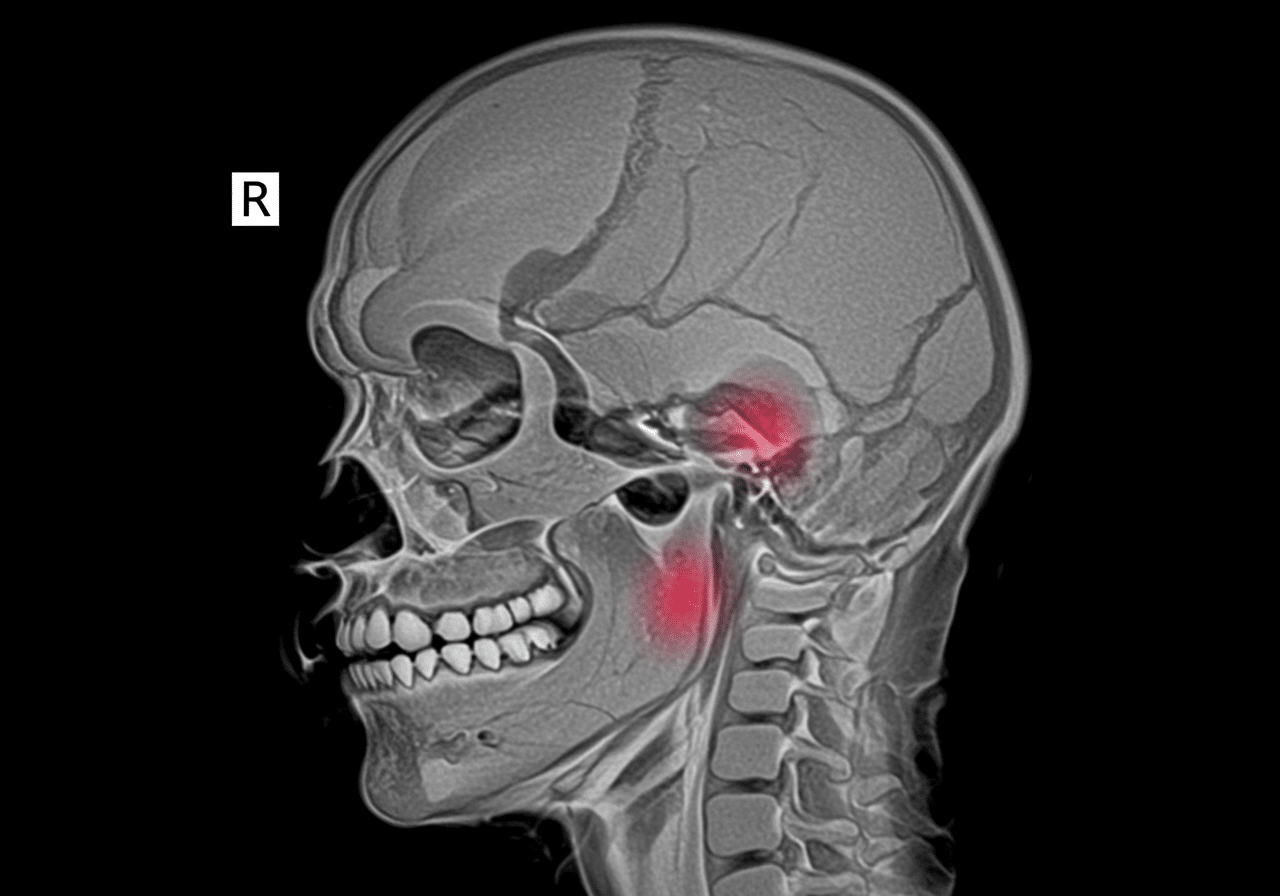

Priority ER's diagnostic capabilities for MRI spine for cord compression or acute back injury exceed Joint Commission standards for emergency departments[14], featuring immediate coordination with affiliated MRI facilities providing stat imaging within 2 hours, 1.5T or 3T MRI scanners with sagittal T1, T2, and STIR sequences visualizing cord signal changes indicating injury (T2 hyperintensity suggesting edema or myelomalacia), and immediate radiologist interpretation identifying disc herniation, hematoma, tumor, or abscess causing cord compression with 93% sensitivity. Our emergency physicians trained in spinal imaging interpretation apply Canadian C-Spine Rules and NEXUS criteria determining which patients require imaging, perform detailed neurological examination using ASIA impairment scale (motor scores 0-5 in key muscles, sensory testing in dermatomes), and initiate methylprednisolone within 8 hours when incomplete cord injury identified on MRI improving neurological recovery by one ASIA grade[15]. The integration of diffusion-weighted imaging (DWI) identifies acute epidural abscess appearing as restricted diffusion, while gadolinium contrast enhancement differentiates tumor from infection and identifies vascular malformations causing cord compression.

Advanced assessment through our comprehensive diagnostic capabilities provides CT myelography when MRI contraindicated by cardiac pacemaker or retained metallic fragments, performing lumbar puncture injecting iodinated contrast outlining spinal cord and detecting compression with 88% sensitivity comparable to MRI. For cervical spine clearance, our emergency physicians apply validated decision rules (NEXUS criteria: midline tenderness, altered consciousness, intoxication, distracting injury, neurological deficit) determining when imaging unnecessary in low-risk patients, while high-risk mechanisms (diving, axial load, high-speed collision) trigger comprehensive CT and MRI evaluation. This comprehensive approach explains why the American College of Radiology appropriateness criteria mandate MRI as gold standard for suspected cord compression, providing superior soft tissue visualization compared to CT identifying epidural collections, ligamentous injury, and cord signal changes invisible on CT requiring MRI for definitive diagnosis guiding neurosurgical decision-making.